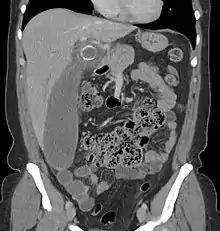

Where it is readily available, computed tomography (CT) has become frequently used, especially in people whose diagnosis is not obvious on history and physical examination. Although some concerns about interpretation are identified, a 2019 Cochrane review found that sensitivity and specificity of CT for the diagnosis of acute appendicitis in adults was high.[61] Concerns about radiation tend to limit use of CT in pregnant women and children, especially with the increasingly widespread usage of MRI.[62][63]

The accurate diagnosis of appendicitis is multi-tiered, with the size of the appendix having the strongest positive predictive value, while indirect features can either increase or decrease sensitivity and specificity. A size of over 6 mm is both 95% sensitive and specific for appendicitis.[64]

However, because the appendix can be filled with fecal material, causing intraluminal distention, this criterion has shown limited utility in more recent meta-analyses.[65] This is as opposed to ultrasound, in which the wall of the appendix can be more easily distinguished from intraluminal feces. In such scenarios, ancillary features such as increased wall enhancement as compared to adjacent bowel and inflammation of the surrounding fat, or fat stranding, can be supportive of the diagnosis. However, their absence does not preclude it. In severe cases with perforation, an adjacent phlegmon or abscess can be seen. Dense fluid layering in the pelvis can also result, related to either pus or enteric spillage. When patients are thin or younger, the relative absence of fat can make the appendix and surrounding fat stranding difficult to see.[65]